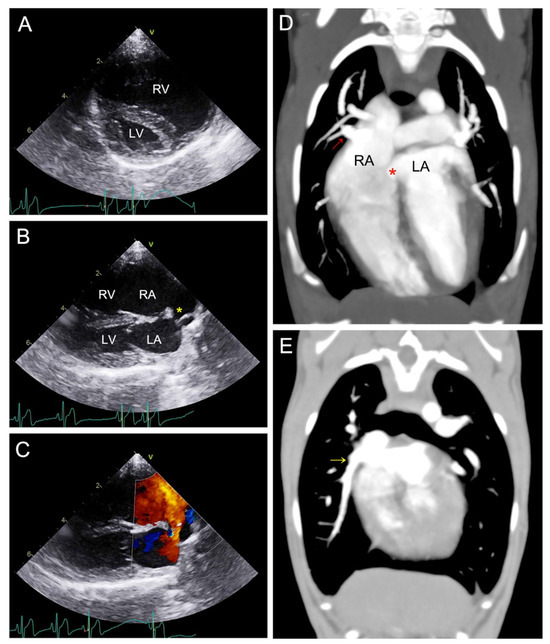

2. Case